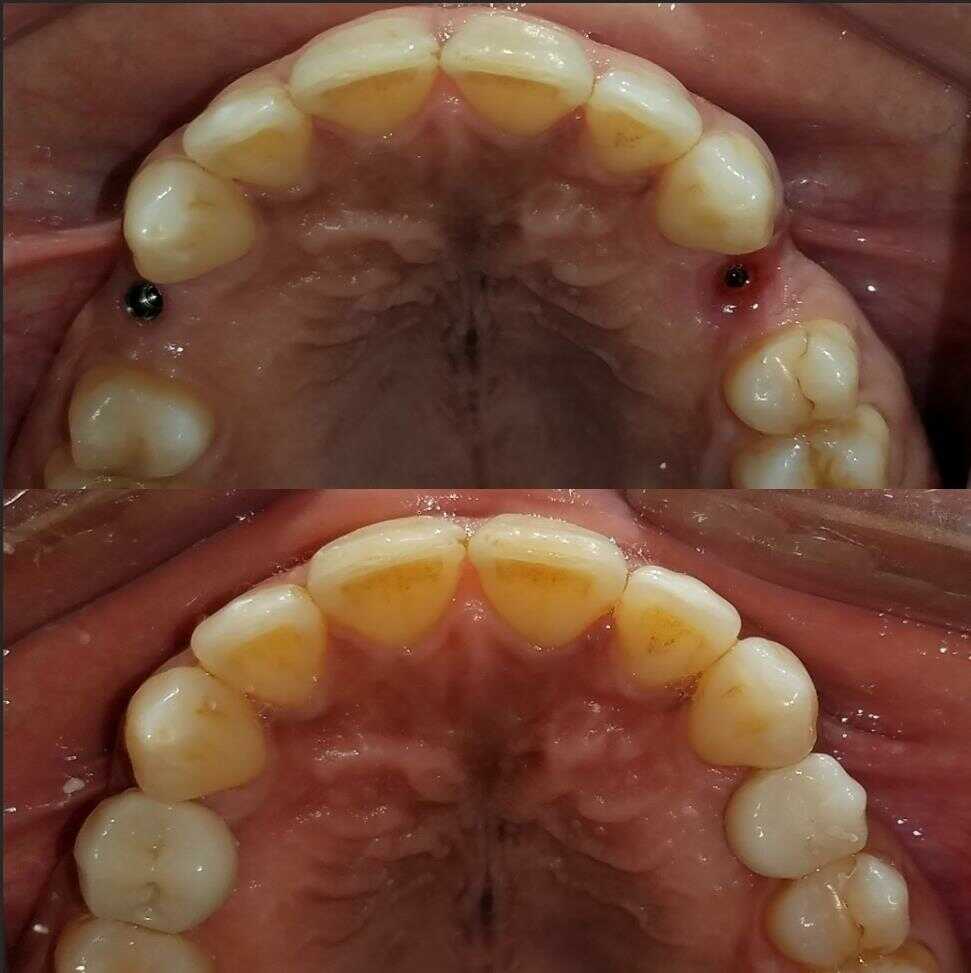

INVISALIGN: before and after

DENTAL CLEANINGS: before and after